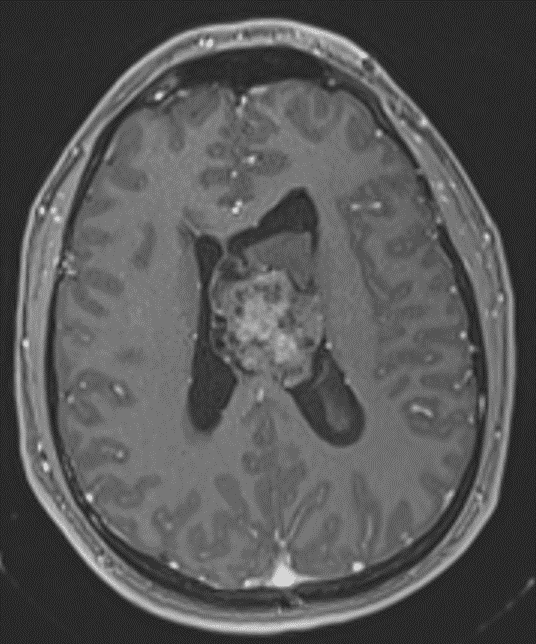

• Mildly FLAIR hyperintense intraventricular mass in the body of the left lateral ventricle measuring 4.3 x 3.7 cm in axial dimensions with heterogeneous corresponding enhancement and restricted diffusion

Corresponding heterogeneous enhancement.